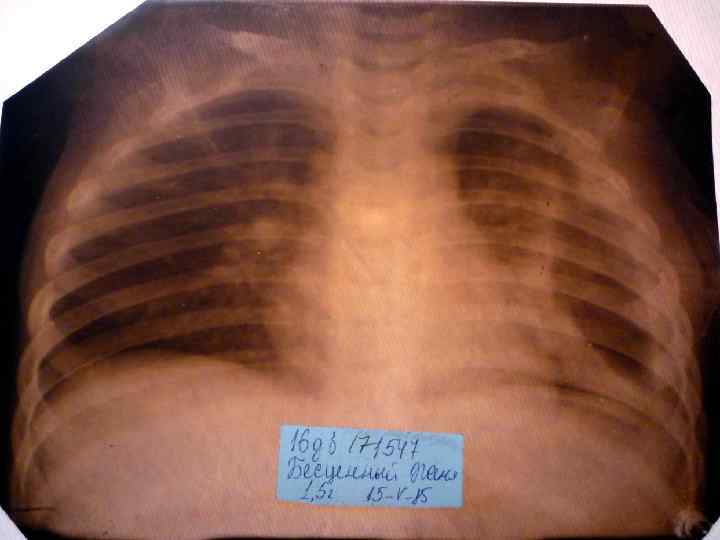

Пневмония Воспалительный процесс в респираторных отделах легкого с наличием внутриальвеолярной экссудации. n Это острое инфекционное заболевание легочной паренхимы, диагностируемое по синдрому дыхательных расстройств и/или физикальным данным при наличии очаговых или инфильтративных изменений на рентгенограмме. n Пневмония – это, прежде всего, клинический диагноз, который ставит врач у постели больного, и только затем подтверждает рентгенологически. n

Пневмония - это неспецифическое воспаление легочной ткани, в основе которого лежат инфекционный токсикоз, дыхательная недостаточность, водно – электролитные и прочие метаболические нарушение с патологическими изменениями во всех органах и системах детского организма. Заболевание диагностируется на основании синдрома дыхательных расстройств и/или физикальных данных и верифицируется рентгенологически выявлением инфильтративных изменений в легких.

Долевая пневмония характеризуется лобарным пневмоническим инфильтратом. Крупозная ( пневмококковая) пневмония диагностируется прежде всего по клиническим данным. Крупозная пневмония сохраняет свою типичную картину пневмококковой пневмонии: острое начало с характерными клиническими данными, циклическое течение, несклонность к деструкции, гомогенной и лобарной инфильтративной тенью при рентгенологическом исследовании. Вместе с тем, широкое использование антибиотиков способствовало значительному снижению числа крупозных пневмоний у детей. Интерстициальная – редкая форма пневмоний, при которой оказывается поражен прежде всего интерстиций. Как правило, интерстициальная пневмония обусловлена вирусами, пневмоцистами, внутриклеточными микроорганизмами и грибами.

Морфологическую форму пневмонии определяют по клинико – рентгенологическим данным: выделяют очаговую, очагово – сливную, долевую ( крупозную), сегментарную и интерстициальную пневмонии. Очаговая – наиболее распространенная форма. Пневмонические очаги чаще бывают размером 1 см и более. Очагово – сливная – инфильтративные изменения в нескольких сегментах или во всей доле легкого, на фоне которых могут быть видны более плотные участки инфильтрации и/или полости деструкции. Сегментарная – в процесс вовлекается весь сегмент, который, как правило, находится в состоянии гиповентиляции, ателектаза. Морфологическая картина воспаления при очаговых и сегментарных пневмониях связана с первичным инфекционным воспалением в бронхах, что дает основание отнести эти варианты поражения легочной ткани к бронхопневмониям, нередко сопровождающихся бронхообструктивным или бронхообтурационным синдромами. В настоящее время данный тип пневмоний у детей встречается наиболее часто.